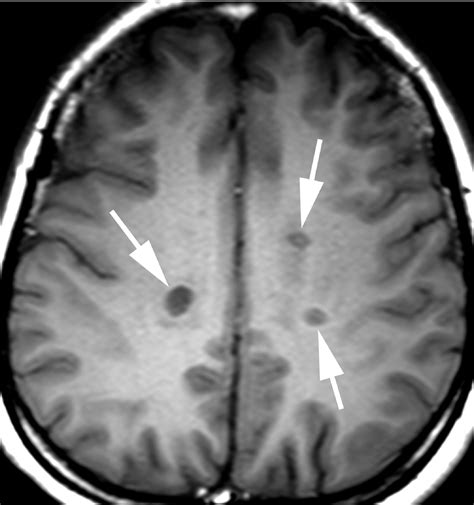

• Multiple Sclerosis (MS): To detect active plaques or lesions caused by the disease.

By highlighting these specific areas, the contrast agent allows radiologists to distinguish healthy tissue from diseased tissue. It acts like a spotlight, making lesions, tumors, or areas of inflammation "light up" on the resulting images. Without this enhancement, subtle abnormalities might remain hidden, leading to potentially delayed or incorrect diagnoses.